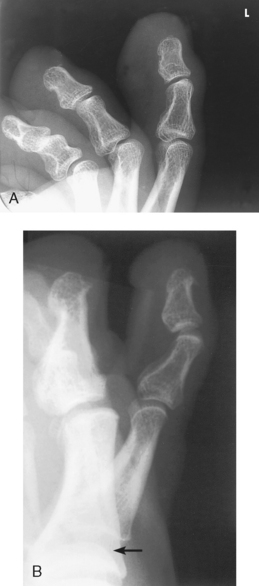

Structures shown: Images show a lateral projection of the phalanges of the toe and the IP articulations projected free of the other toes (Figs. 6-29 to 6-33).